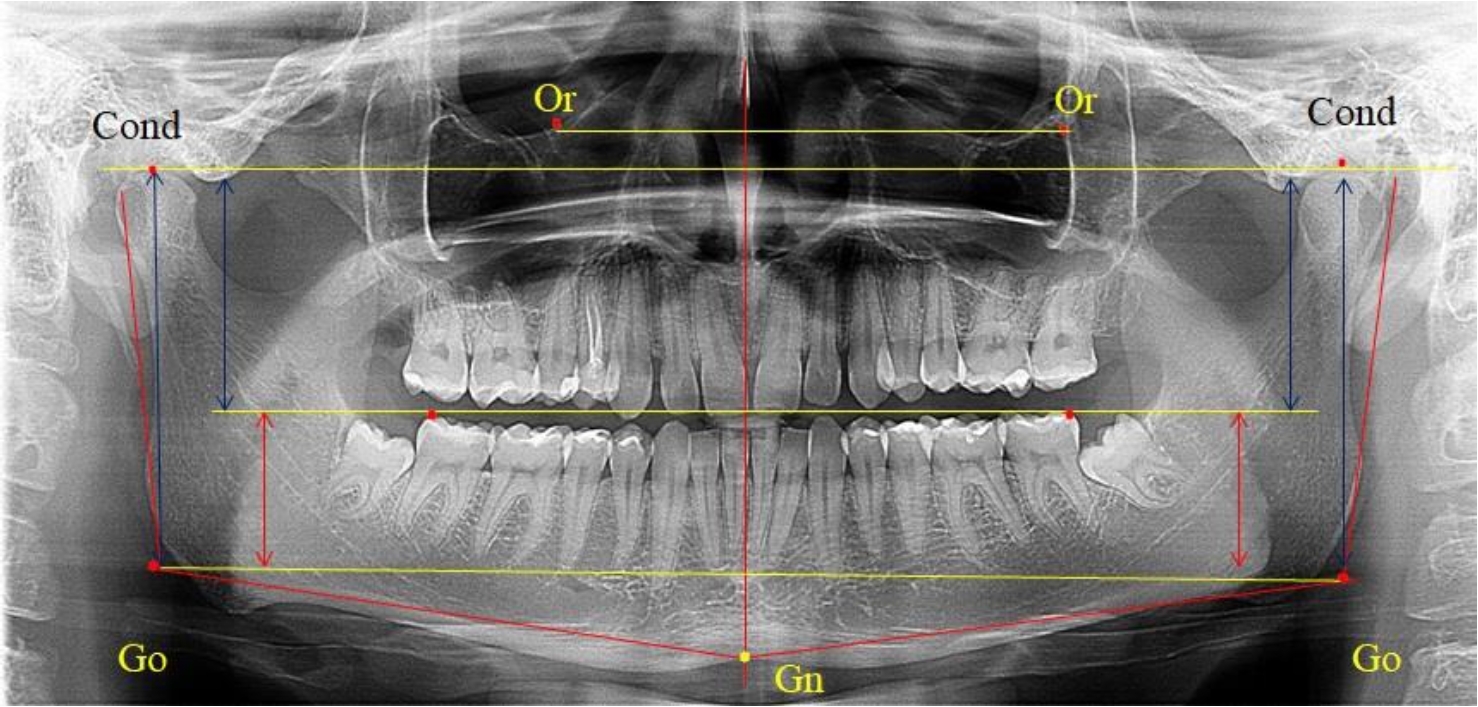

На ортопантомограмме использовали аналогичные суставные точки Cond на каждой стороне, их соединяли между собой суставной линией Cond-Cond.

Касательная к ветви нижней челюсти соединяла выступающие точку. При построении касательной к телу челюсти проводили в обе стороны линии от точки Gn, расположенной в нижней центральной части подбородочного симфиза, до выступающей нижней точки угла челюсти. Касательные линии при пересечении определяли конструктивную точку гонион Go. Соединение гониональных точек определяло положение гониональной линии Go-Go. При соединении окклюзионных точек hPOcP получали окклюзионную горизонталь (рис. 1). Измеряли расстояние между горизонталями в области ветвей нижней челюсти. Статистический анализ проводили в программе Microsoft Excel. Составляли вариационные ряды с последующим расчетом среднего значения, стандартного отклонения и ошибки среднего ±m. Также оценивали максимальные и минимальные значения величин. Определи относительные величины соотношения верхней и нижней частей ветви нижней челюсти.

Рис. 1. Метод измерения высоты ветви нижней челюсти на телерентгенограмме (а) и ортопантомограмме (б)

Во 2-ю подгруппу был включен 21 комплект телерентгенограмм и ортопантомограмм [или (28,38 ± 5,24) %], на которых средняя величина отношения верхней части ветви к нижней составляла 1,63 ± 0,03, что было достоверно меньше показателя, полученного по группе в среднем и в 1-й подгруппе.

Визуально параметры ветви отличались от первой группы (рис. 3).

Рис. 3. ОПТГ пациента 2-й группы с уменьшенным коэффициентом соотношения частей ветви нижней челюсти

Высота ветви составляла (62,75 ± 1,42) мм и достоверных различий по этому показателю не отмечено. Максимальная высота была 73 мм, а минимальная – 55 мм. Высота верхней части составляла (38,81 ± 0,76) мм, что было достоверно меньше, чем у людей 1-й подгруппы.

В то же время высота нижнего отдела ветви была (23,94 ± 0,73) мм, и показатель отличался в большую сторону по сравнению с аналогичным размеров в 1-й подгруппе.